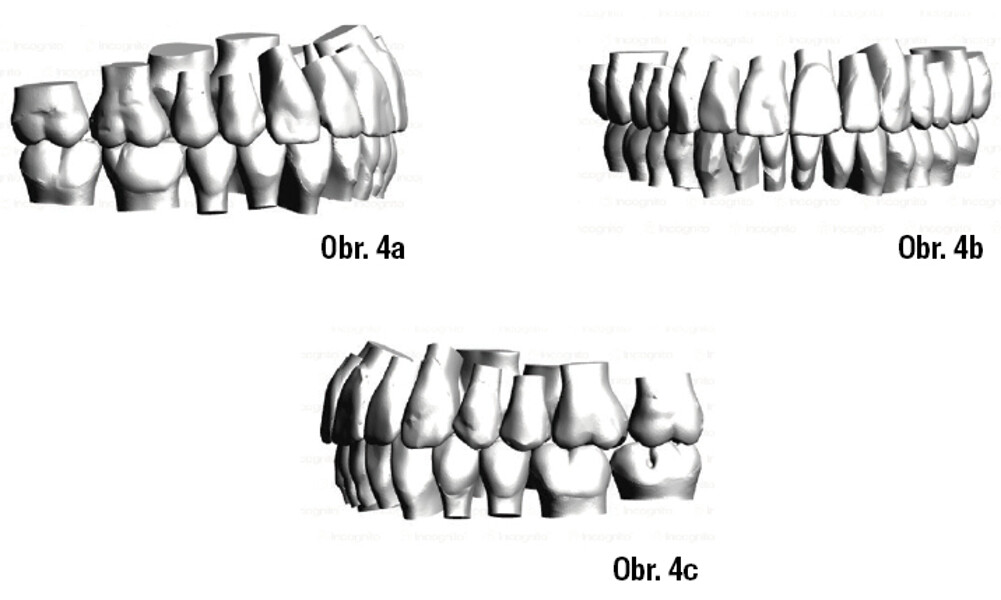

Lingvální zámky 3M™ Incognito™ System a kombinovaná ortodontickochirurgická terapie